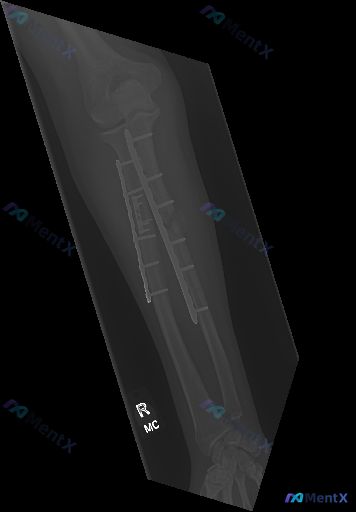

右侧前臂(桡骨与尺骨)双骨折术后内固定状态。

- 内固定:桡骨、尺骨干均可见钢板+螺钉固定,钢板跨越骨干中段,目前钢板螺钉位置固定,未见明显移位、松动或断裂征象。

- 骨折愈合:骨折断端处骨痂形成尚不明显(骨痂影较淡),骨折线仍隐约可见。

- 关节:近端肱桡/尺桡关节、远端桡腕关节及腕骨排列大致正常,未见明显脱位/半脱位,关节间隙无明显异常增宽或狭窄。

- 软组织:层次尚清晰,未见明显广泛肿胀,未见明确异常气体或不透光异物。

目前影像报告给出的总结是“右前臂尺桡骨骨折术后(内固定术后);内固定在位,骨折断端对位尚可,但骨折线尚存在,骨性愈合仍在进行中”。